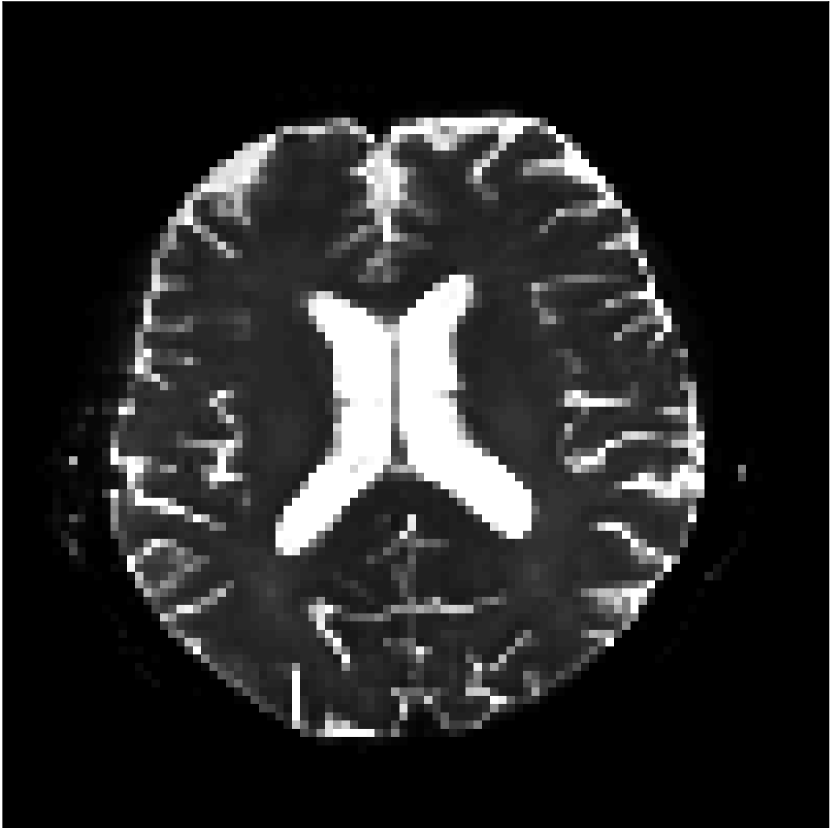

Figure 9 shows parameter maps for the different methods without partial Fourier (No PF) and with 5/8ths partial Fourier (5/8 PF). Mean diffusivities calculated from the raw DWI data (Raw) show notable noise and Gibbs ringing artifacts, while this is substantially removed with the state-of-the-art (SoA) method. However, the state-of-the-art method begins to lose its ability to compensate for the Gibbs ringing and resolution loss when partial Fourier is utilized in the acquisition. The effects of partial Fourier increases are primarily evident in the enlargement of the lateral ventricles and the presence of black lines in the vicinity of the lateral ventricles. The MCNN model is able to compensate somewhat for the ringing effects, but begins to introduce substantial artifacts at the 5/8ths partial Fourier factor, whereas the CCNN model continues to give high-quality mean parameter maps across all PF factors.

Raw

SoA

MCNN

Standard PF

CCNN

s/mm2

No PF

MD, m2/ms

5/8 PF

FA

MK

Similar trends are observed in the other diffusion parameter maps.